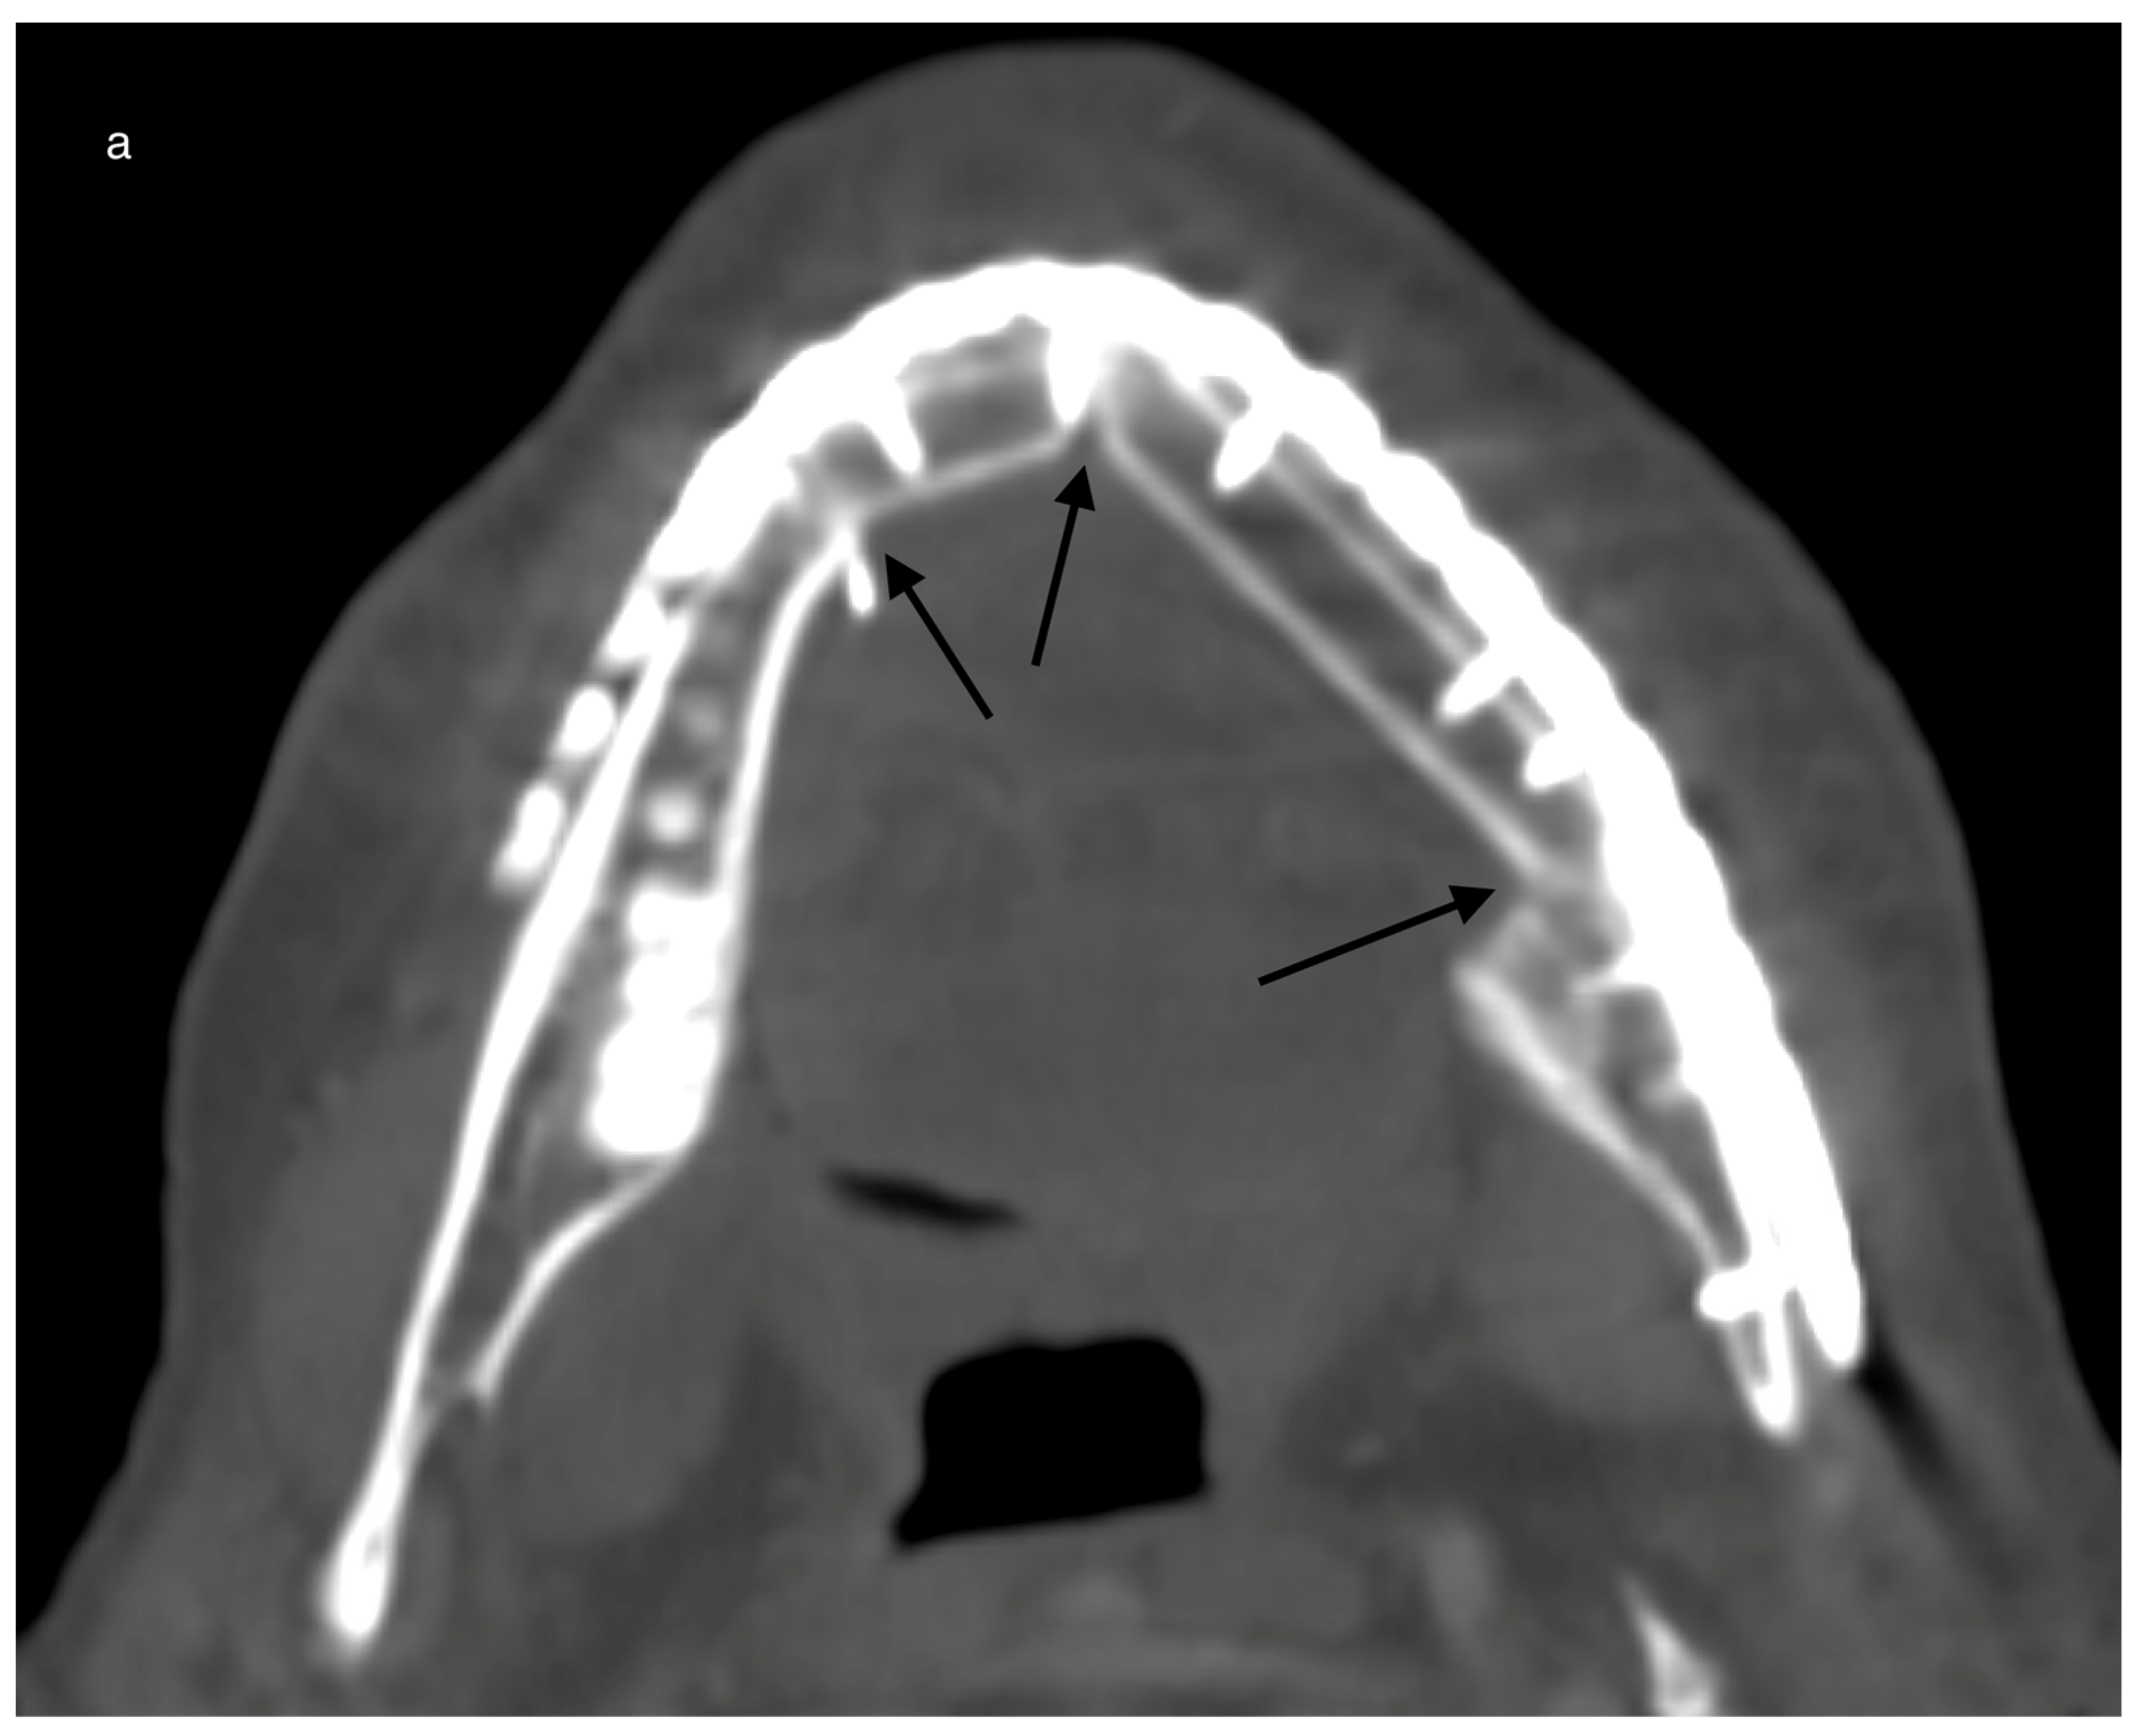

| HU gain overall for grouping locations horizontally #1 per day (p = 0.003) | ||||

| basal | reference | |||

| cranial | 5.26 | −53.34 | 63.86 | 0.860 |

| middle | 114.06 | 45.35 | 182.76 | 0.001 |

| HU gain overall for grouping locations vertically #2 per day (p = 0.005) | ||||

| Vestibular (+) | reference | |||

| Lingual (*) | −98.72 | −157.31 | −40.13 | 0.001 |

| Middle (#) | −86.70 | −155.41 | −17.99 | 0.013 |